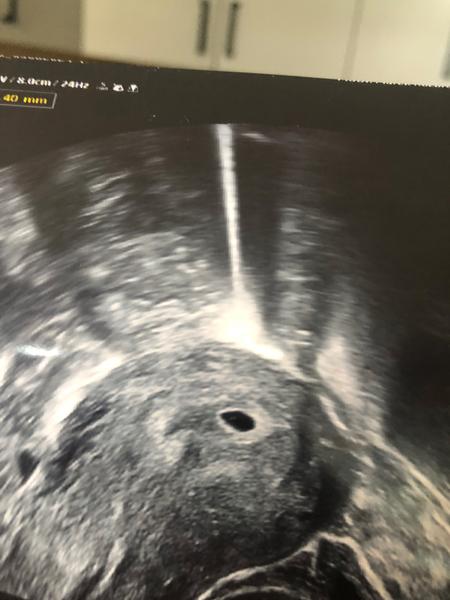

Gestační váček v 6. týdnu těhotenství. Co dál?

@sabinazidkova20 Uplně nevím ovulaci, kdy byla. Ale podle ultrazvuku jsem 6. týden. Tak já nevím.

Jen neviděla plod, ale říkala, že žloutkový váček vidí, ale potom mi řekla, že to může být i anembryomola. Tak jsem z toho smutná.

Musela jsem jít na prohlídku už teď, mám za sebou už 2 potraty. Tak proto jsem šla už teď. No uvidíme. Ale váček je v pořádku, vypadá tak jak má vypadat? Je už dost veliký 18mm, ale plod neviděla.

A vypadá ten váček v pořádku? Má takhle vypadat?…